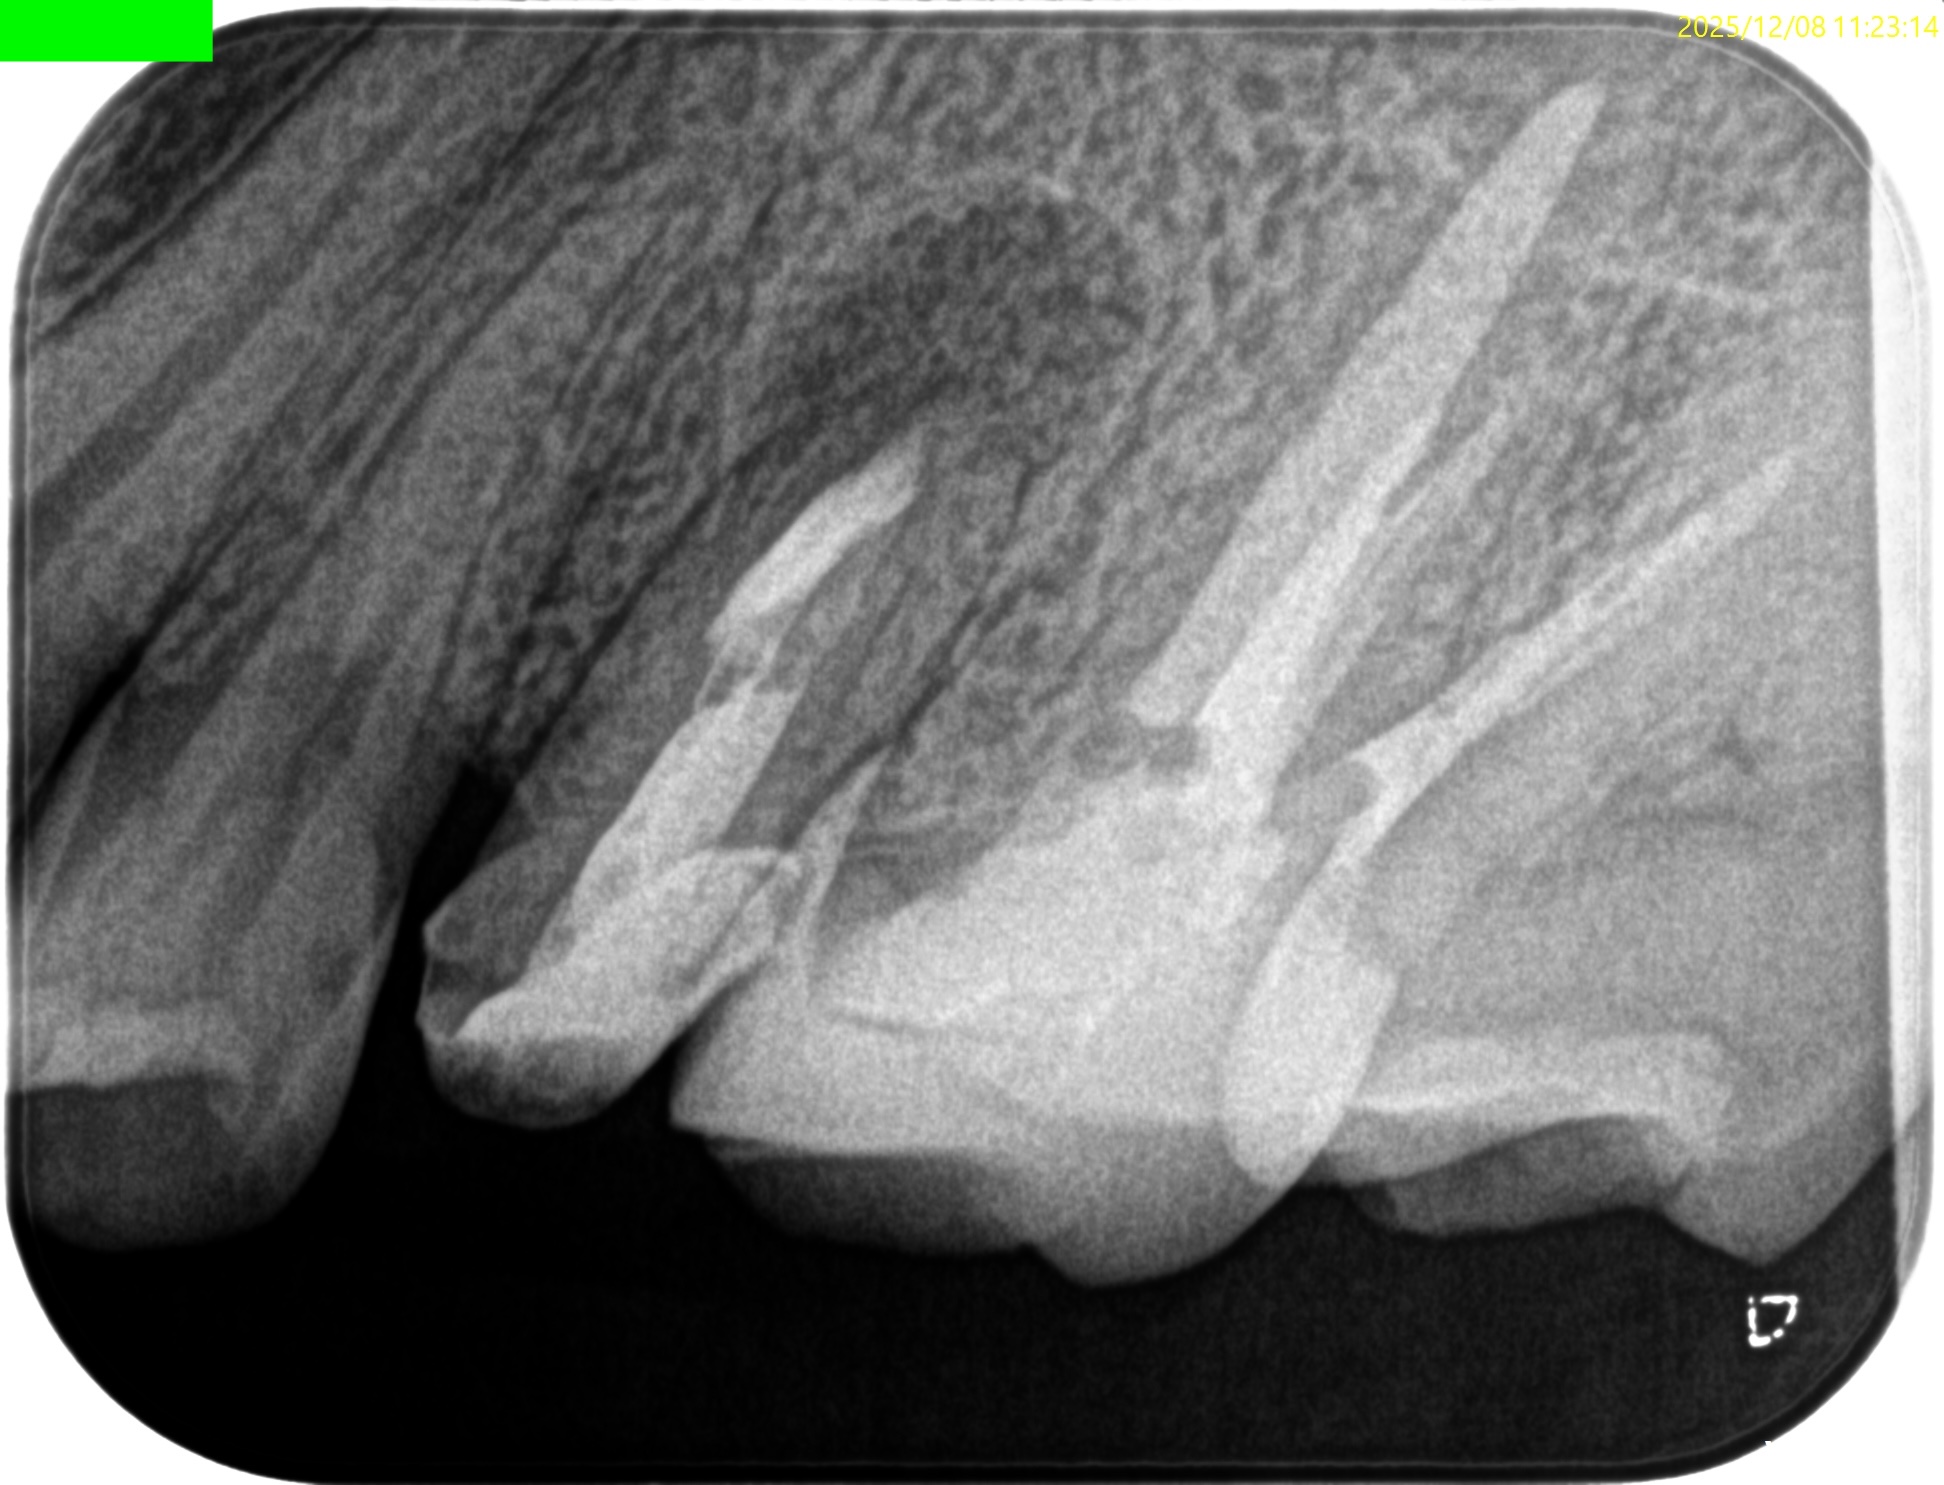

初診時と比較した。

劇的に歯槽骨が回復している。

治療前・直後と5ヶ月後を比較した。